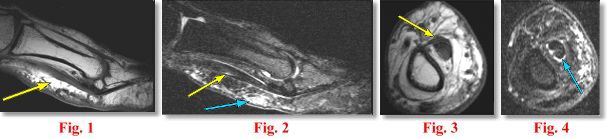

MRI FINDINGS: The MRI was performed on AIC’s high-field 1.5 Tesla short-bore Siemens Symphony. An ultra small, high-resolution digit coil was utilized to evaluate the thumb. A small field of view of only 6 cm was used. Slice thickness of 0.8 mm to 2 mm were selected. Sagittal, axial and coronal 2 mm T1W and fat suppressed T2W Fat Sat and coronal 0.8 mm DESS were obtained. Fig. 1 (Sagittal T1W) shows moderate thickening of the flexor pollicis tendons along the proximal phalanx with some increased signal. Fig. 2 (sagittal T2 Fat Sat) shows the same with subcutaneous edema and small amount of fluid in the tendon sheath. It is difficult to separate the superficial and deep flexor tendons. Fig. 3 and Fig. 4 are the corresponding axial images demonstrating the same findings.

DIAGNOSIS: These findings are c/w tendinitis/tenosynovitis of the flexor tendons typical of a “trigger thumb.”